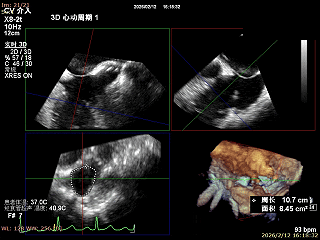

二尖瓣三维视图

术前CT评估

收缩期周长:173mm 面积2217mm²。非右冠优势型,RCA走行中段之后未见瓣环平面冠脉显影。术中冠脉影响风险较低。

术前瓣环面积

术后瓣环面积